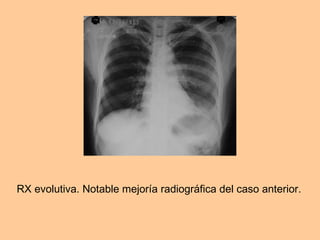

RX evolutiva. Notable mejoría radiográfica del caso anterior.

Fem. 39 años. MC: fiebre de 40oC, dolor en punta de costado izquierdo, expectoración verdosa. Pérdida del conocimiento. Extenso bloque neumónico de los 2/3 inferiores del campo pulmonar izquierdo. Broncograma aéreo. Ligero derrame pleural asociado